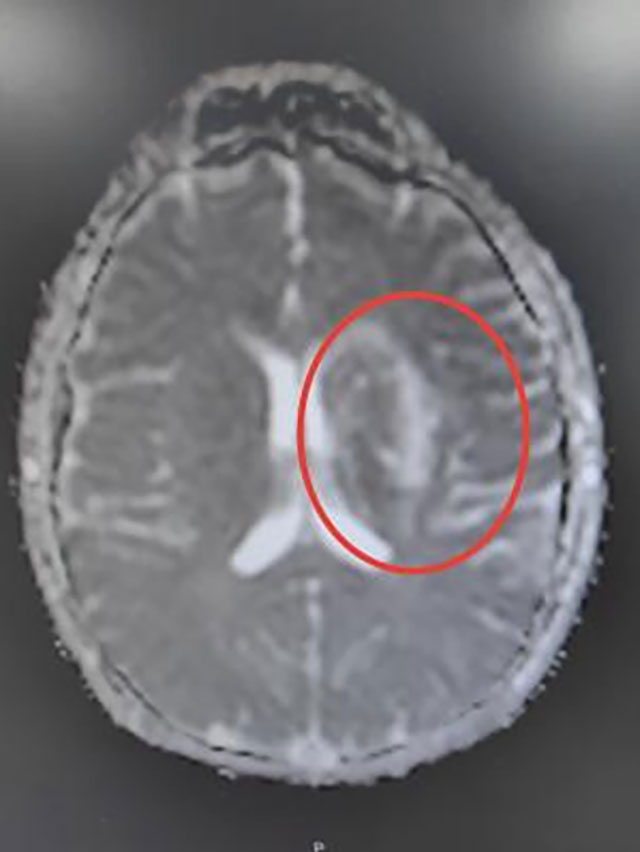

●头颅增强MRI:左侧额顶颞岛叶、基底节区、侧脑室旁及大脑中脚异常信号,部分病灶弥散受限,左侧外囊软化表现;

头颅MRI影像表现

最后考虑诊断为卵圆孔未闭合所致的脑梗死(心源性栓塞型),经中西医结合治疗后小王同学好转出院,并拟于后期接受卵圆孔未闭封堵术治疗。